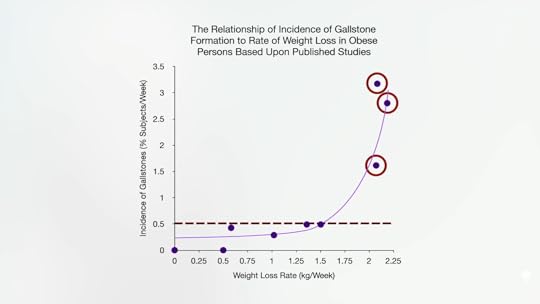

Ironically, rapid weight loss may also be a trigger. Half a pound (1.5 kg) a day has been deemed the upper limit for medically safe weight loss, based on gallstone formation. Ultrasound studies found that, above that, the chance of new gallstones can go from less than 1 in 200 a week to closer to 1 in 40, as shown below and at 1:59.